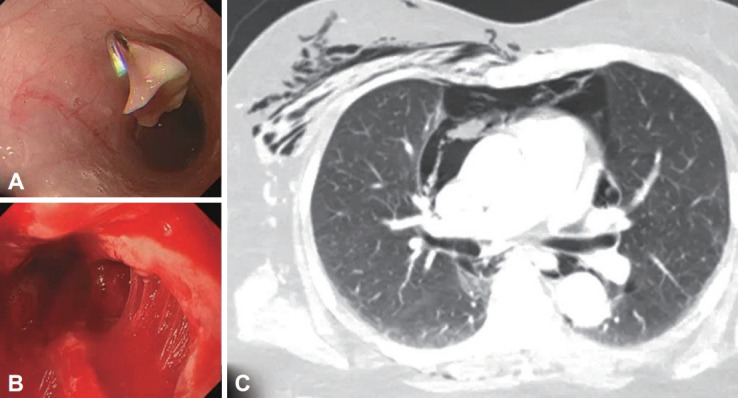

Esophageal Rupture Occurred During the Endoscopic Removal of a Lodged Denture.